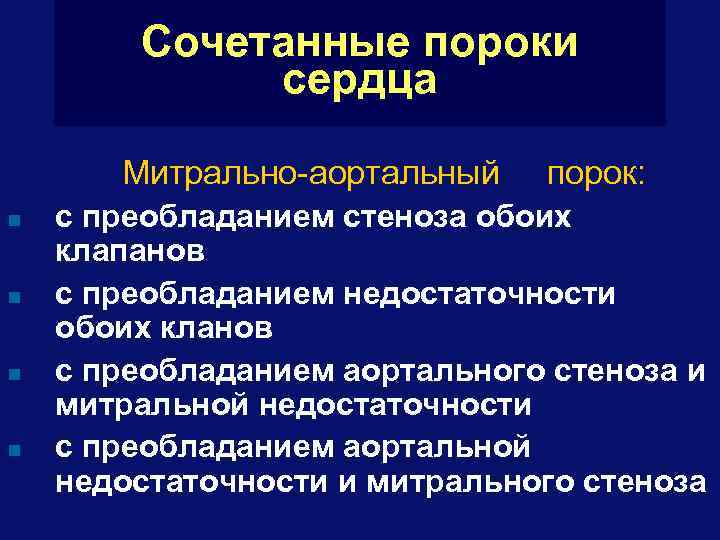

Сочетанные пороки сердца Митрально-аортальный n n порок: с преобладанием стеноза обоих клапанов с преобладанием недостаточности обоих кланов с преобладанием аортального стеноза и митральной недостаточности с преобладанием аортальной недостаточности и митрального стеноза